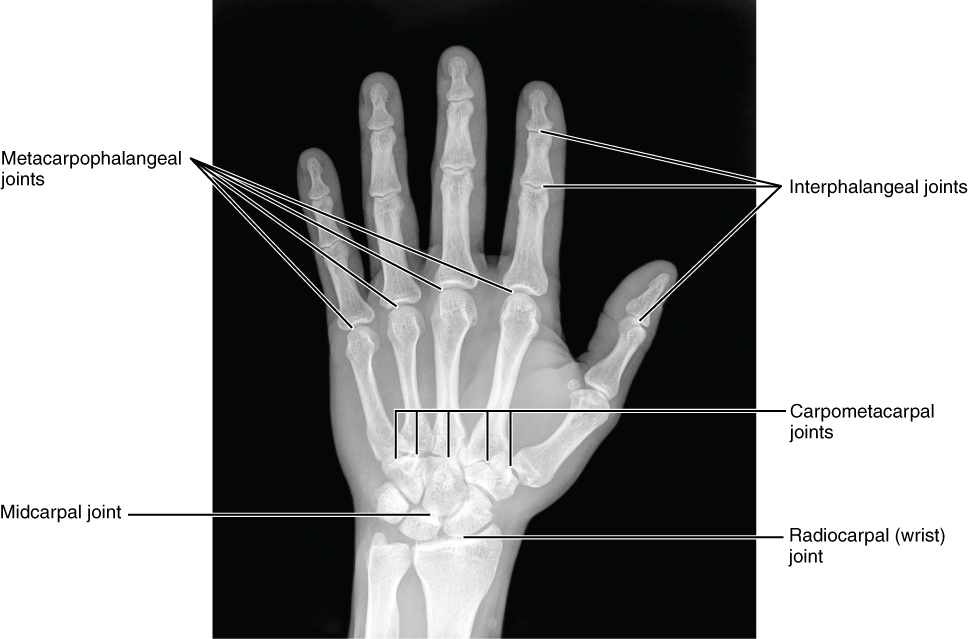

The carpal bones form the base of the hand. This can be seen in the radiograph (X-ray image) of the hand that shows the relationships of the hand bones to the skin creases of the hand (see Figure 8.2.4). Within the carpal bones, the four proximal bones are united to each other by ligaments to form a unit. Only three of these bones, the scaphoid, lunate, and triquetrum, contribute to the radiocarpal joint. The scaphoid and lunate bones articulate directly with the distal end of the radius, whereas the triquetrum bone articulates with a fibrocartilaginous pad (creating a space in the X-ray in Figure 8.2.4 between the ulna and the triquetrum). The distal end of the ulna thus does not directly articulate with any of the carpal bones.

The four distal carpal bones are also held together as a group by ligaments. The proximal and distal rows of carpal bones articulate with each other to form the midcarpal joint (see Figure 8.2.4). Together, the radiocarpal and midcarpal joints are responsible for all movements of the hand at the wrist. The distal carpal bones also articulate with the metacarpal bones of the hand.

The palm of the hand contains five elongated metacarpal bones. These bones lie between the carpal bones of the wrist and the bones of the fingers and thumb (see Figure 8.2.3). The proximal end of each metacarpal bone articulates with one of the distal carpal bones. Each of these articulations is a carpometacarpal joint (see Figure 8.2.4). The expanded distal end of each metacarpal bone articulates at the metacarpophalangeal joint with the proximal phalanx bone of the thumb or one of the fingers. The distal end also forms the knuckles of the hand, at the base of the fingers. The metacarpal bones are numbered 1–5, beginning at the thumb.

The fingers and thumb contain 14 bones, each of which is called a phalanx bone (plural = phalanges), named after the ancient Greek phalanx (a rectangular block of soldiers). The thumb (pollex) is digit number 1 and has two phalanges, a proximal phalanx, and a distal phalanx bone (see Figure 8.2.3). Digits 2 (index finger) through 5 (little finger) have three phalanges each, called the proximal, middle, and distal phalanx bones. An interphalangeal joint is one of the articulations between adjacent phalanges of the digits (see Figure 8.2.4).